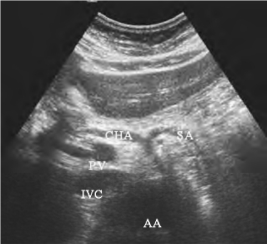

1.27.3三、正常超声表现